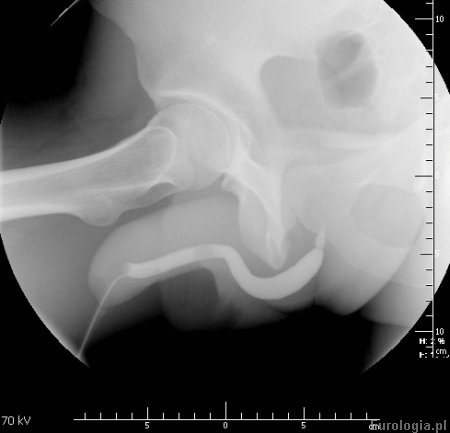

Urethrografia pozwala na ocenę nieprawidłowości w budowie cewki moczowej takich jak zwężenie, uchyłek cewki oraz pozwala na ocenę stopnia, lokalizacji i długości uszkodzenia cewki moczowej w urazach.

Fot. Uretrografia